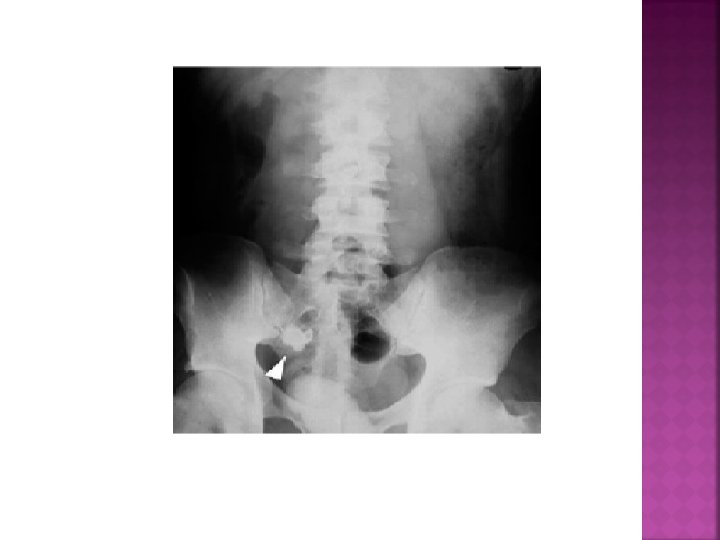

LABORATUVAR Direkt grafi (Fekalit, sağ alt kadranda hava sıvı seviyesi, Psoas gölgesi silinebilir, skolyoz)

AKUT APANDİSİT